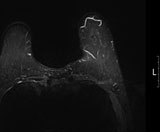

유방 MRI

유방암을 진단함에 있어서 최신의 미세침 흡인세포검사, 정위적 (Stereotactic) 조직검사 및 맘모튬 조직검사를 사용하고 있으며, 그로 인해서 진단의 정확도와 절제 성공률을 높이고 있습니다. 유방암을 확진하면 그다음으로는 병기를 결정하기 위해서 여러 가지 검사를 시행합니다. PET와 MRI, 전신 골스캔 검사, 폐, 복부 CT 스캔 검사 등의 다양한 검사를 통해서 전이 여부 및 환자의 수술 전 병기를 정확하게 확인합니다.